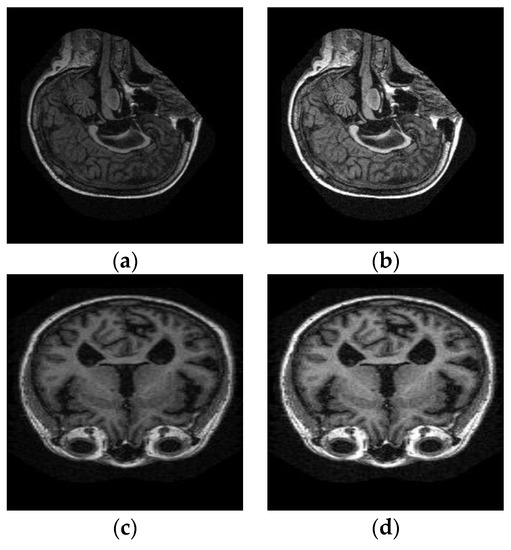

4.6.1. Pre-Processing Results